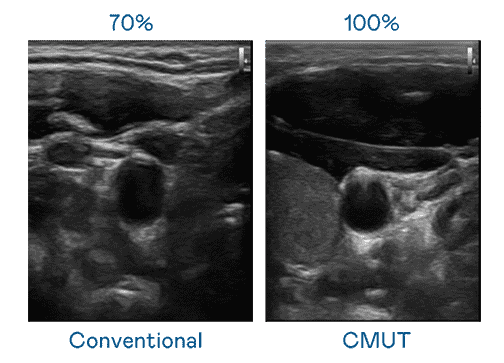

CMUT 技术是一种用电容式微机电元件来产生超音波讯号的技术。。。。与传统 PZT 压电式技术相比,,CMUT 频宽增加 30%,,,,更宽频的超音波讯号让影像解析度大幅提升,,,,是实现高影像品质医疗超音波扫描、、促进精准医疗发展的关键技术。。。。

大频宽带来超清晰影像

超音波影像的解析度高低,,,首先取决于探头能发出的讯号频宽。。。。尊时凯龙 CMUT 可提供高清晰的超音波讯号,,,,提供高频宽、、高灵敏度、、、、影像纹理细节更高的超音波影像,,,协助医护人员缩短影像判读时间及利用精准的医疗影像进行诊断。。。。